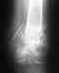

У мужа в 49 лет перелом шейки бедра, прооперировали - поставили 3 винта. 06.11.2008 прошло 5 мес после операции. Делали снимки, врач сказал, что процесс заростания вяло пошел. После последнего снимка врач сказал, что в шейке бедра остеопороз.

снимки Уважаемые профессионалы выскажите мнение, что еще можно предпринять для спасения сустава

снимок - 5 мес после операции

http://s43.radikal.ru/i101/0811/25/d816f52517a9.jpg

снимок - 4 мес после операции

http://s47.radikal.ru/i117/0811/25/cabdb6d35fa6.jpg

снимок - 3 мес после операции

http://s61.radikal.ru/i173/0811/9c/ef70f0bed90e.jpg

перелом

http://i065.radikal.ru/0811/ac/52dab04052ba.jpg

сразу после операции

К сожалению, без повторной операции нету шансов на хороший исход. Фиксация винтами несостоятельна. Эндопротезирование, видимо, оптимальный путь.